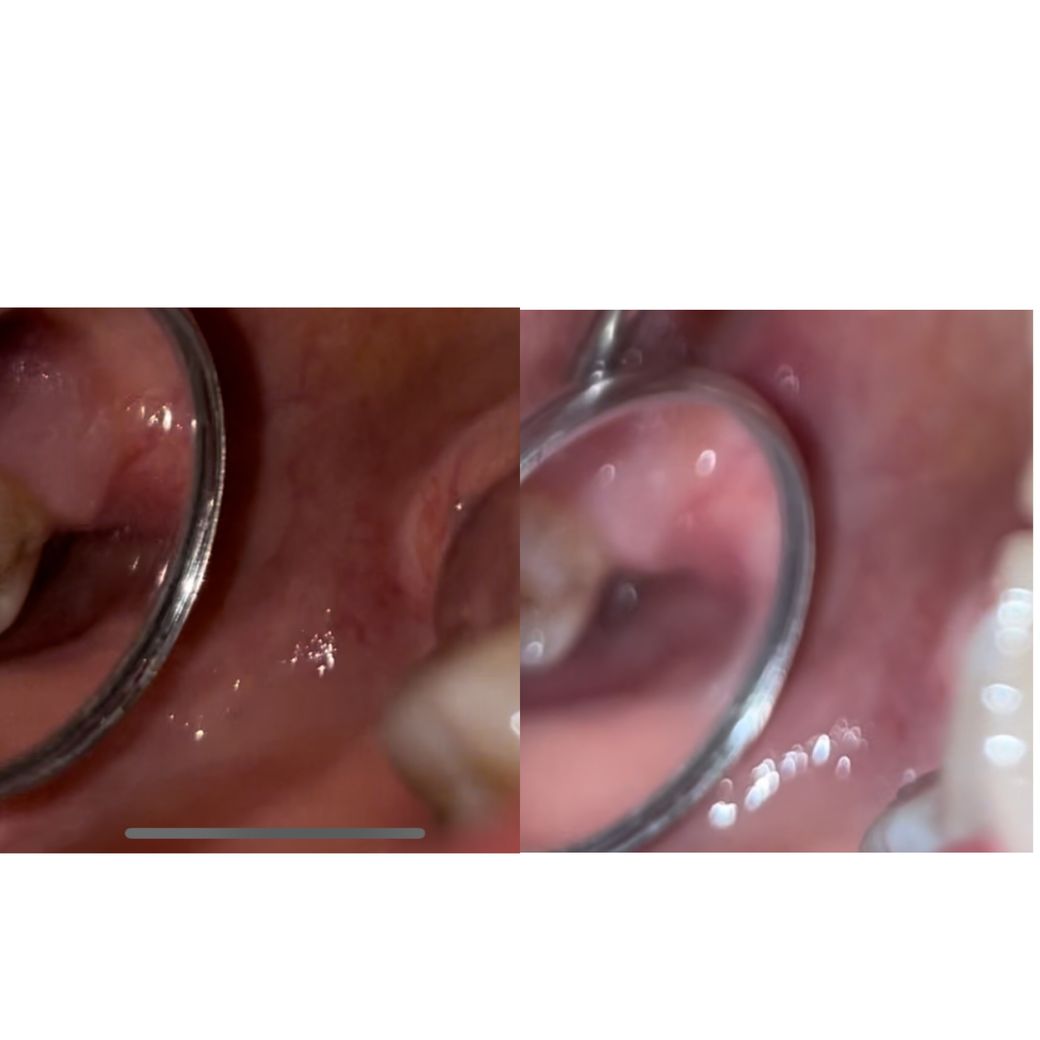

사진 자세히 찍는다고 찍었는데 침이 좀 고여있고 치아가 더러워서 혐오스러울수 있습니다!! ㅜㅜ

사진은 시간이 지나는 순서대로 올렸고 제일 마지막 사진엔 침이 좀 고여있는데.. 하얀색 저건 뭔지도 궁금하고요 ㅜ ㅜ

중간사진엔 볼록볼록 위아래 있던거같은데 아래에 있던 볼록이에서 마지막 사진 처럼 하얀게 튀어나온덜까요??